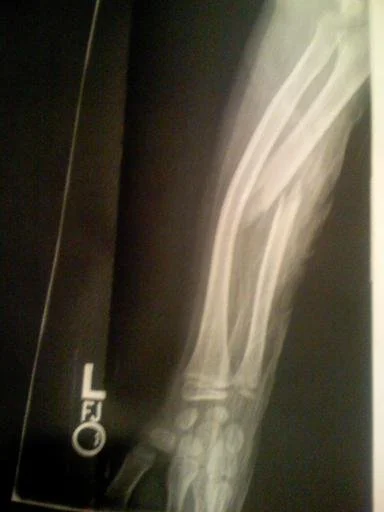

Hand Therapy & Upper Extremity Rehab

Expert care for the shoulder, elbow, wrist, and hand.

Recovering from injury, surgery, or chronic conditions? Lymph-A-Hand helps restore strength, mobility, and function.

Injured and can't get to a clinic? Lymph-A-Hand brings expert, one-on-one rehab to your home—blending clinical precision with holistic care for your hand, wrist, elbow, and shoulder.

Hand & Upper Extremity Therapy Evaluation – 60–75 minutes

Ideal for orthopedic issues, injury, or post-op recovery of the arm, wrist, shoulder, or hand. Includes assessment of mobility, strength, sensation, scar tissue, and function to build a targeted therapy plan.